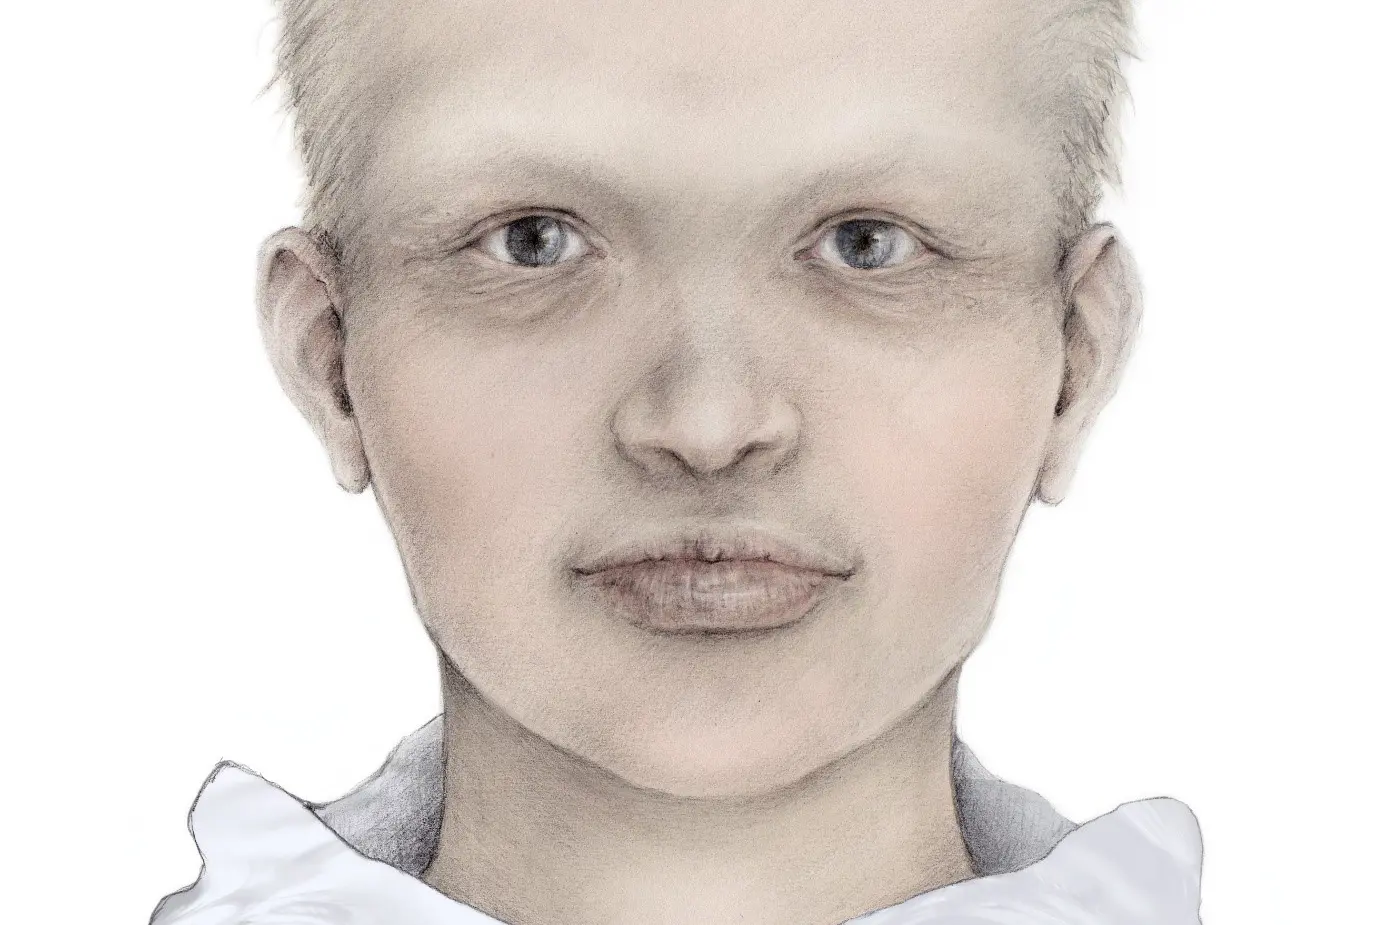

Gutter med HED har ofte en tydelig panne, tynt og lyst hår på hodet og lite behårede øyenbryn, tørr hud, spesielt synlig under øynene. Leppene er ofte relativt fyldige. Illustratør: Malin Bernas-Theisen, TAKO-senteret.